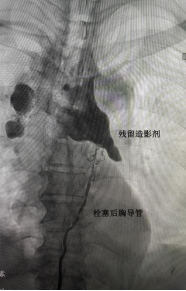

经介入手术室梅娜护士长,白婷副护士长协调下,我科汤瑞祥主治医师率先成功开展胸导管栓塞术。超声引导下细针穿刺双侧腹股沟淋巴结成功后,缓慢经淋巴结注入造影剂。造影剂下显露胸导管走行及漏点位置。DSA下经腹穿刺腹部淋巴管成功后置入导丝及微导管。于微导管内注入生物胶。注入完成后造影显示胸导管破损处栓塞确切。术后在科室护理人员精心护理下,患者介入后第2天引流液即转为正常并顺利拔除胸腔引流管。患者体表创伤仅为细针穿刺损伤。